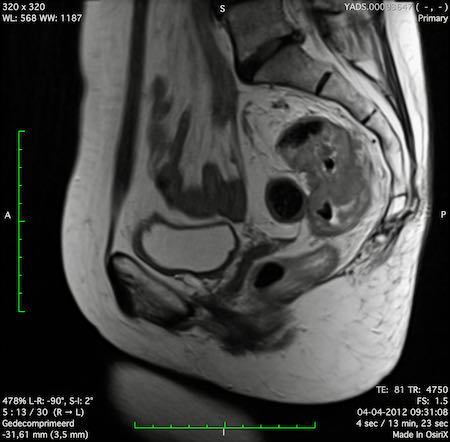

Hình ảnh

Các hình ảnh được cung cấp cho thấy ung thư biểu mô tế bào nhẫn với tình trạng dày lan tỏa thành trực tràng, hình ảnh bia bắn điển hình, và sự xâm lấn mỡ mạc treo trực tràng.